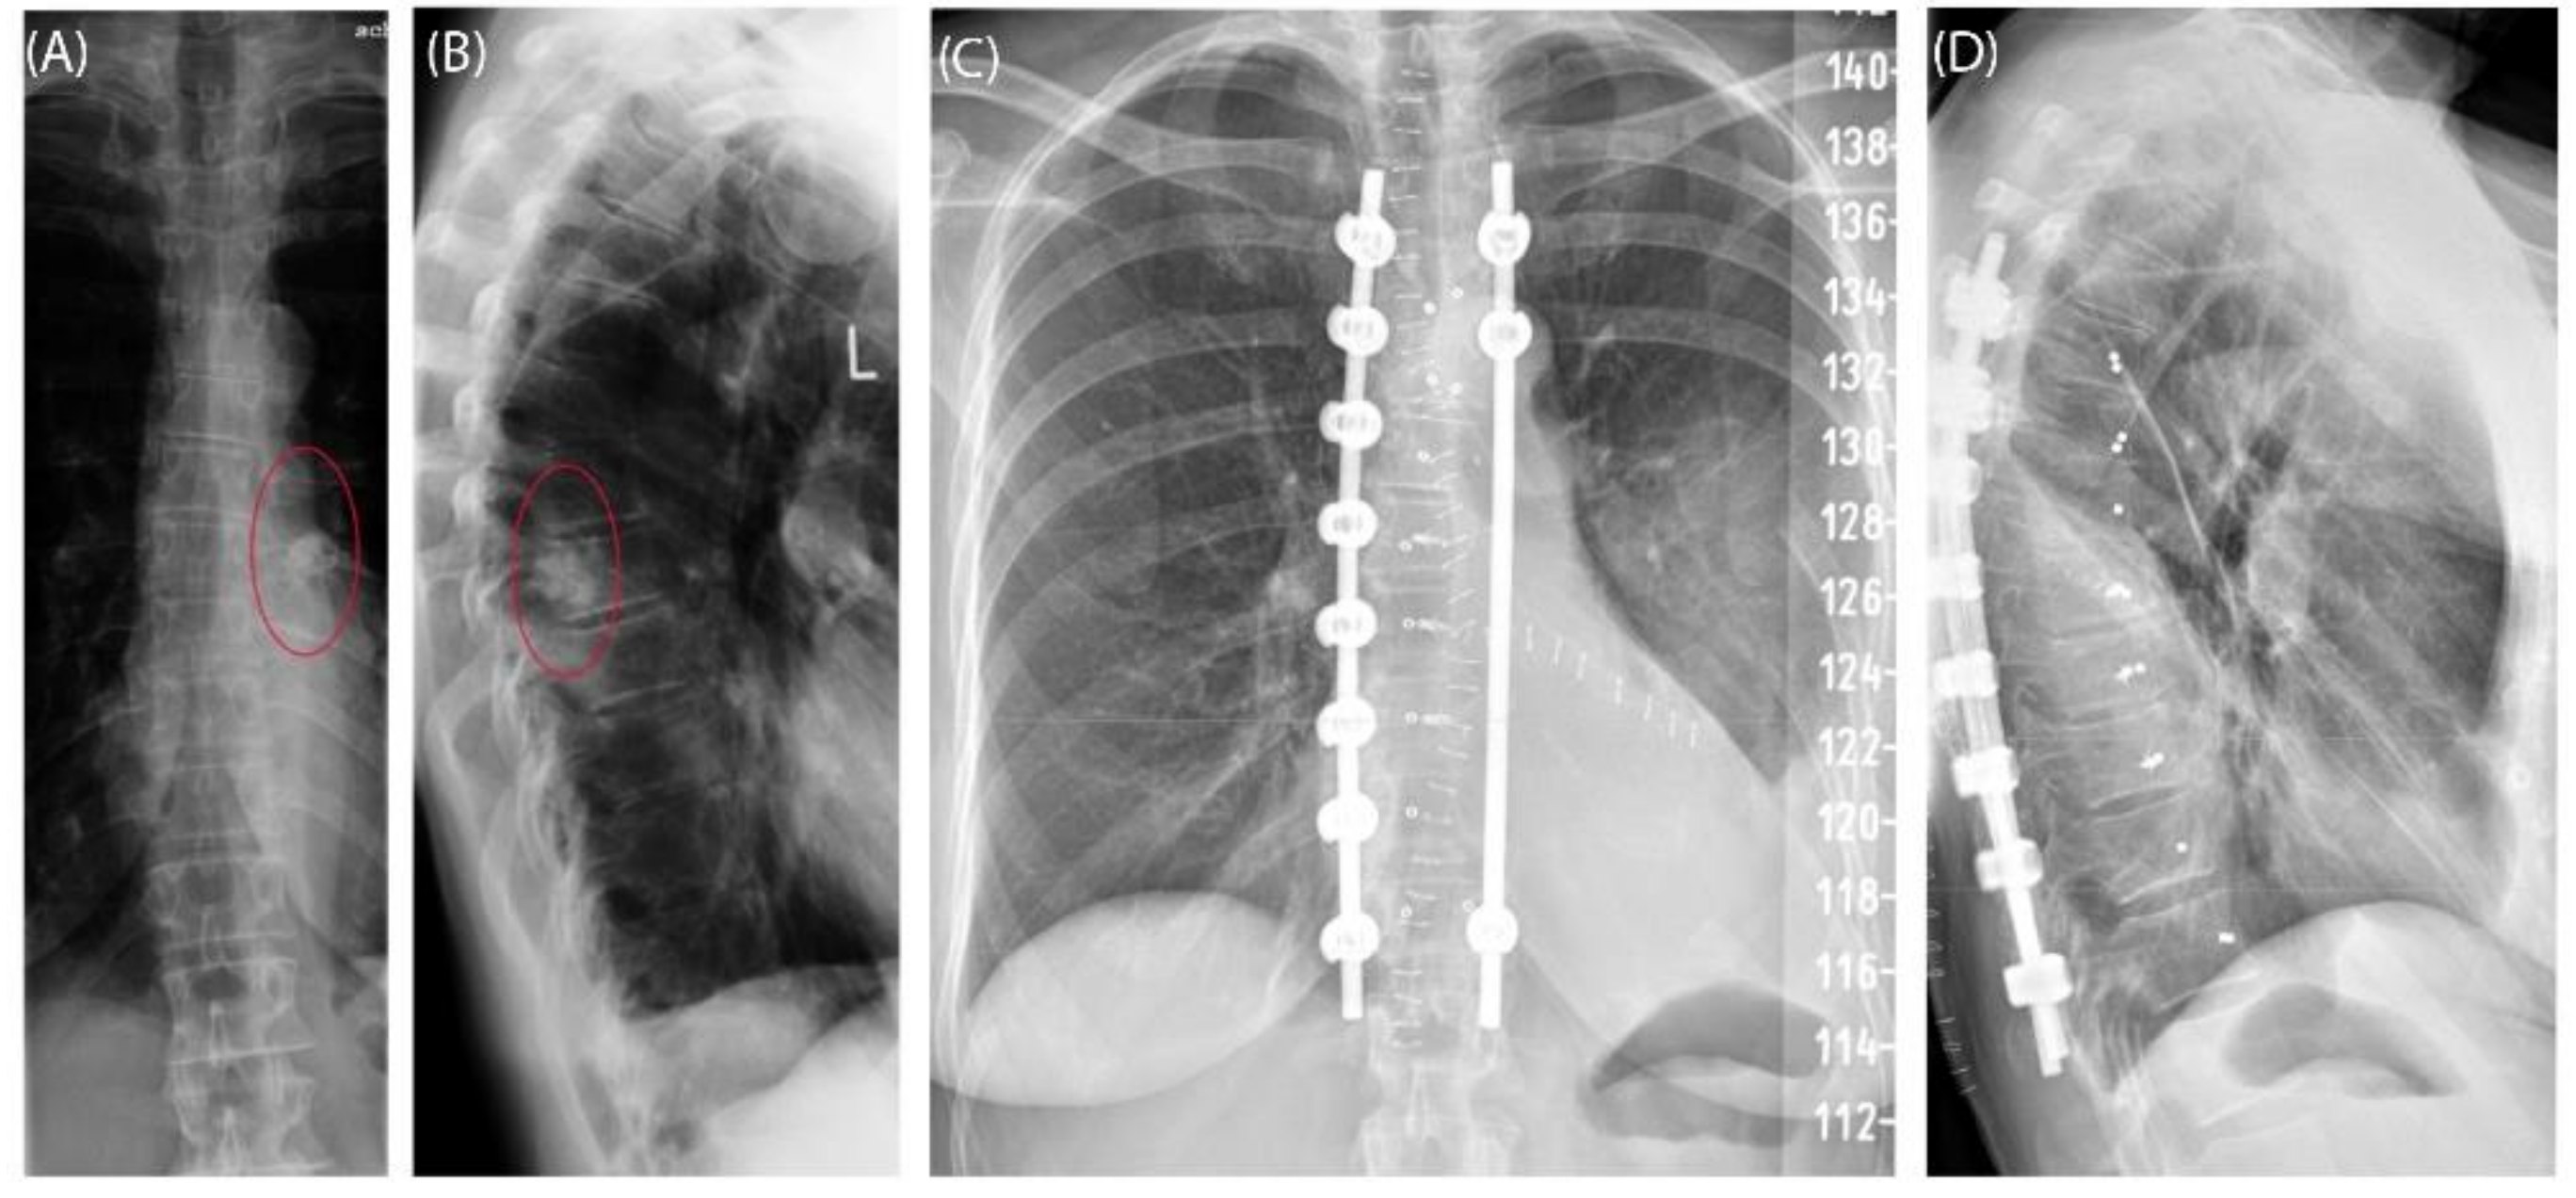

Case 3 involved a 63-year-old female patient with a diagnosed inner thoracic chondrosarcoma (G2) of the 9th left rib. The soft tissue component extended from the 7th to the 11th rib next to the aorta and lungs (Figure 5). After CT-MRI fusion and planning, marginal resection was possible by combining a partial corpectomy T7–T11 with laminectomy T7–T11 and partial resection of ribs 7–11 on the left side. Reconstruction was carried out by instrumentation spondylodesis with a screw-rod system from T5-T11 and extensive coverage with bovine pericardium (Baxter, Deerfield, IL USA) (Figure 6). The postoperative histopathological examinations confirmed tumor-free resection margins and revealed a high-grade tumor (G3). After adjuvant radiation and a four-month postoperative follow-up, there was no sign of local recurrence. The patient returned to daily life without any sensomotoric deficit.

Figure 6. Case 3: Preoperative radiographs in frontal (A) and lateral (B) views, red circles indicate the bony tumor mass; postoperative radiographs in frontal (C) and lateral (D) views.